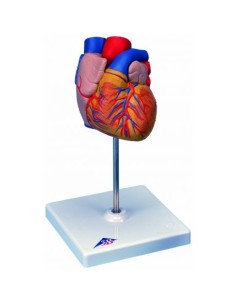

Dal cranio in 22 parti con incastri magnetici ai modelli di colonna vertebrale, da quelli di articolazioni a quelli di cuore, ogni pezzo della nostra collezione è progettato per un’immersione totale nello studio dell’anatomia umana. I nostri modelli, realizzati tramite scansioni di ossa vere, garantiscono un’esperienza tattile autentica e una fedeltà di peso quasi identica agli originali.

Essenziali per studenti e professionisti, i nostri modelli anatomici sono strumenti didattici che permettono di osservare le strutture anatomiche con precisione, eliminando la necessità di dissezioni o studi invasivi. Sono inoltre utili per spiegare ai pazienti le patologie, rendendo la comunicazione più efficace e risparmiando tempo prezioso.